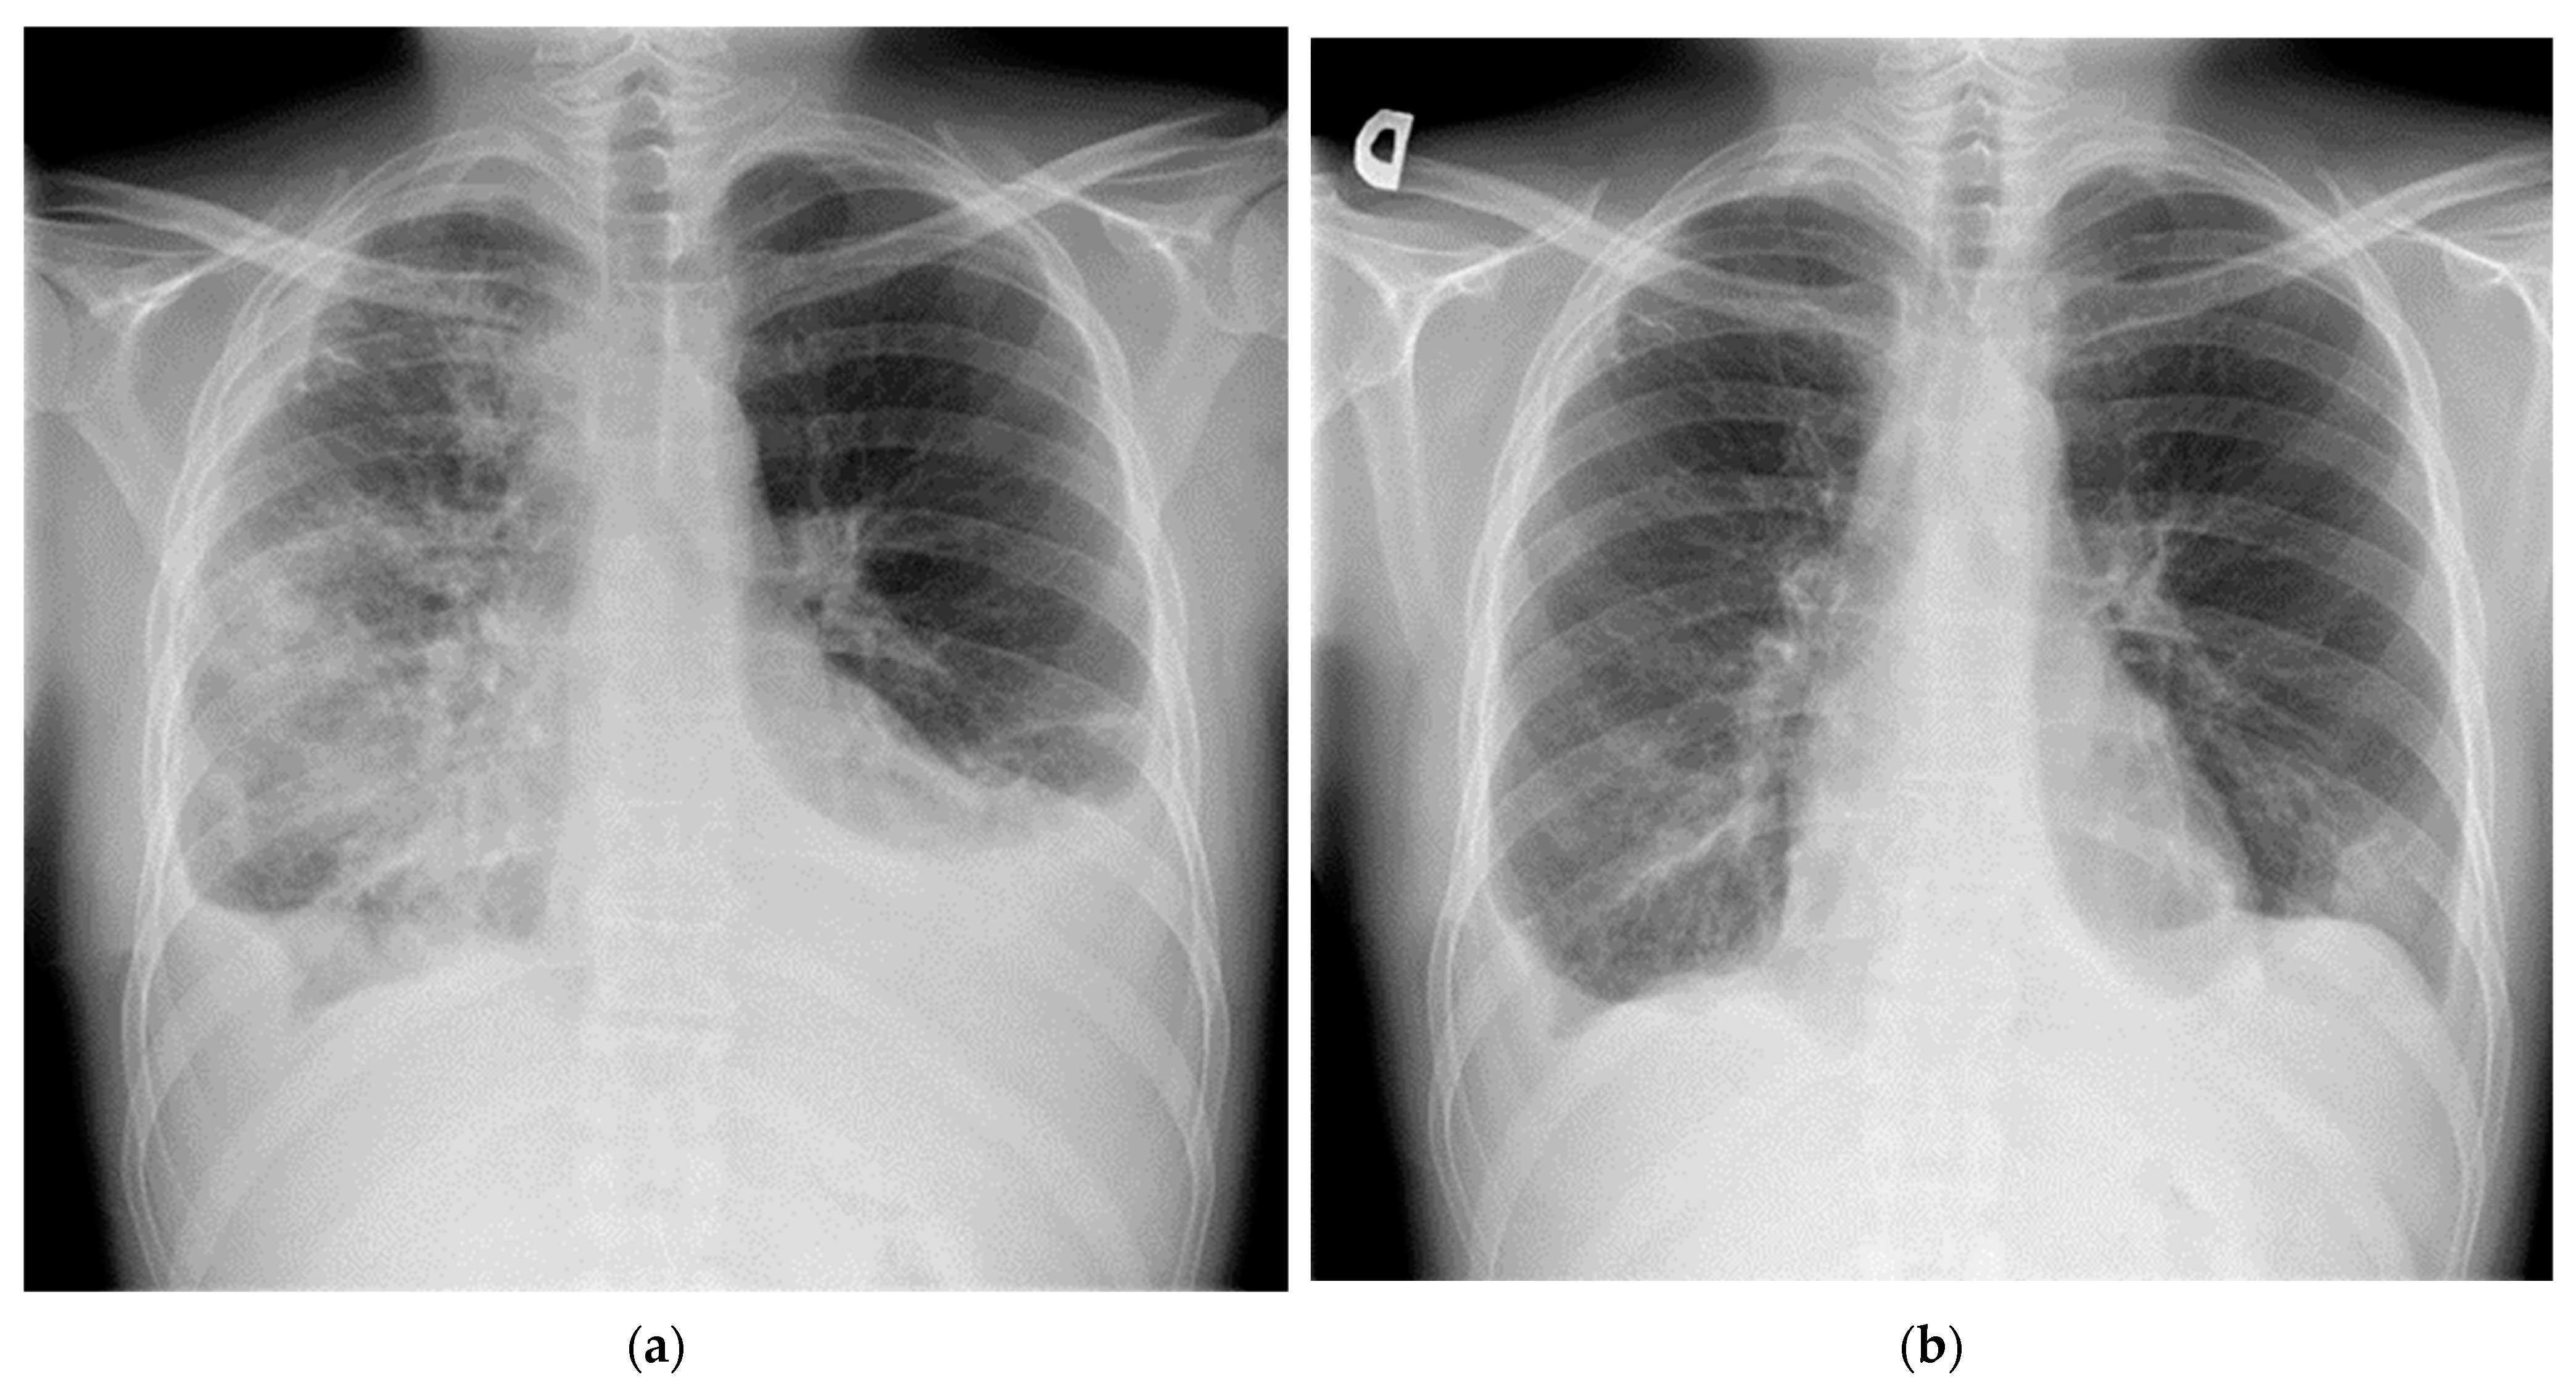

2. Case Report